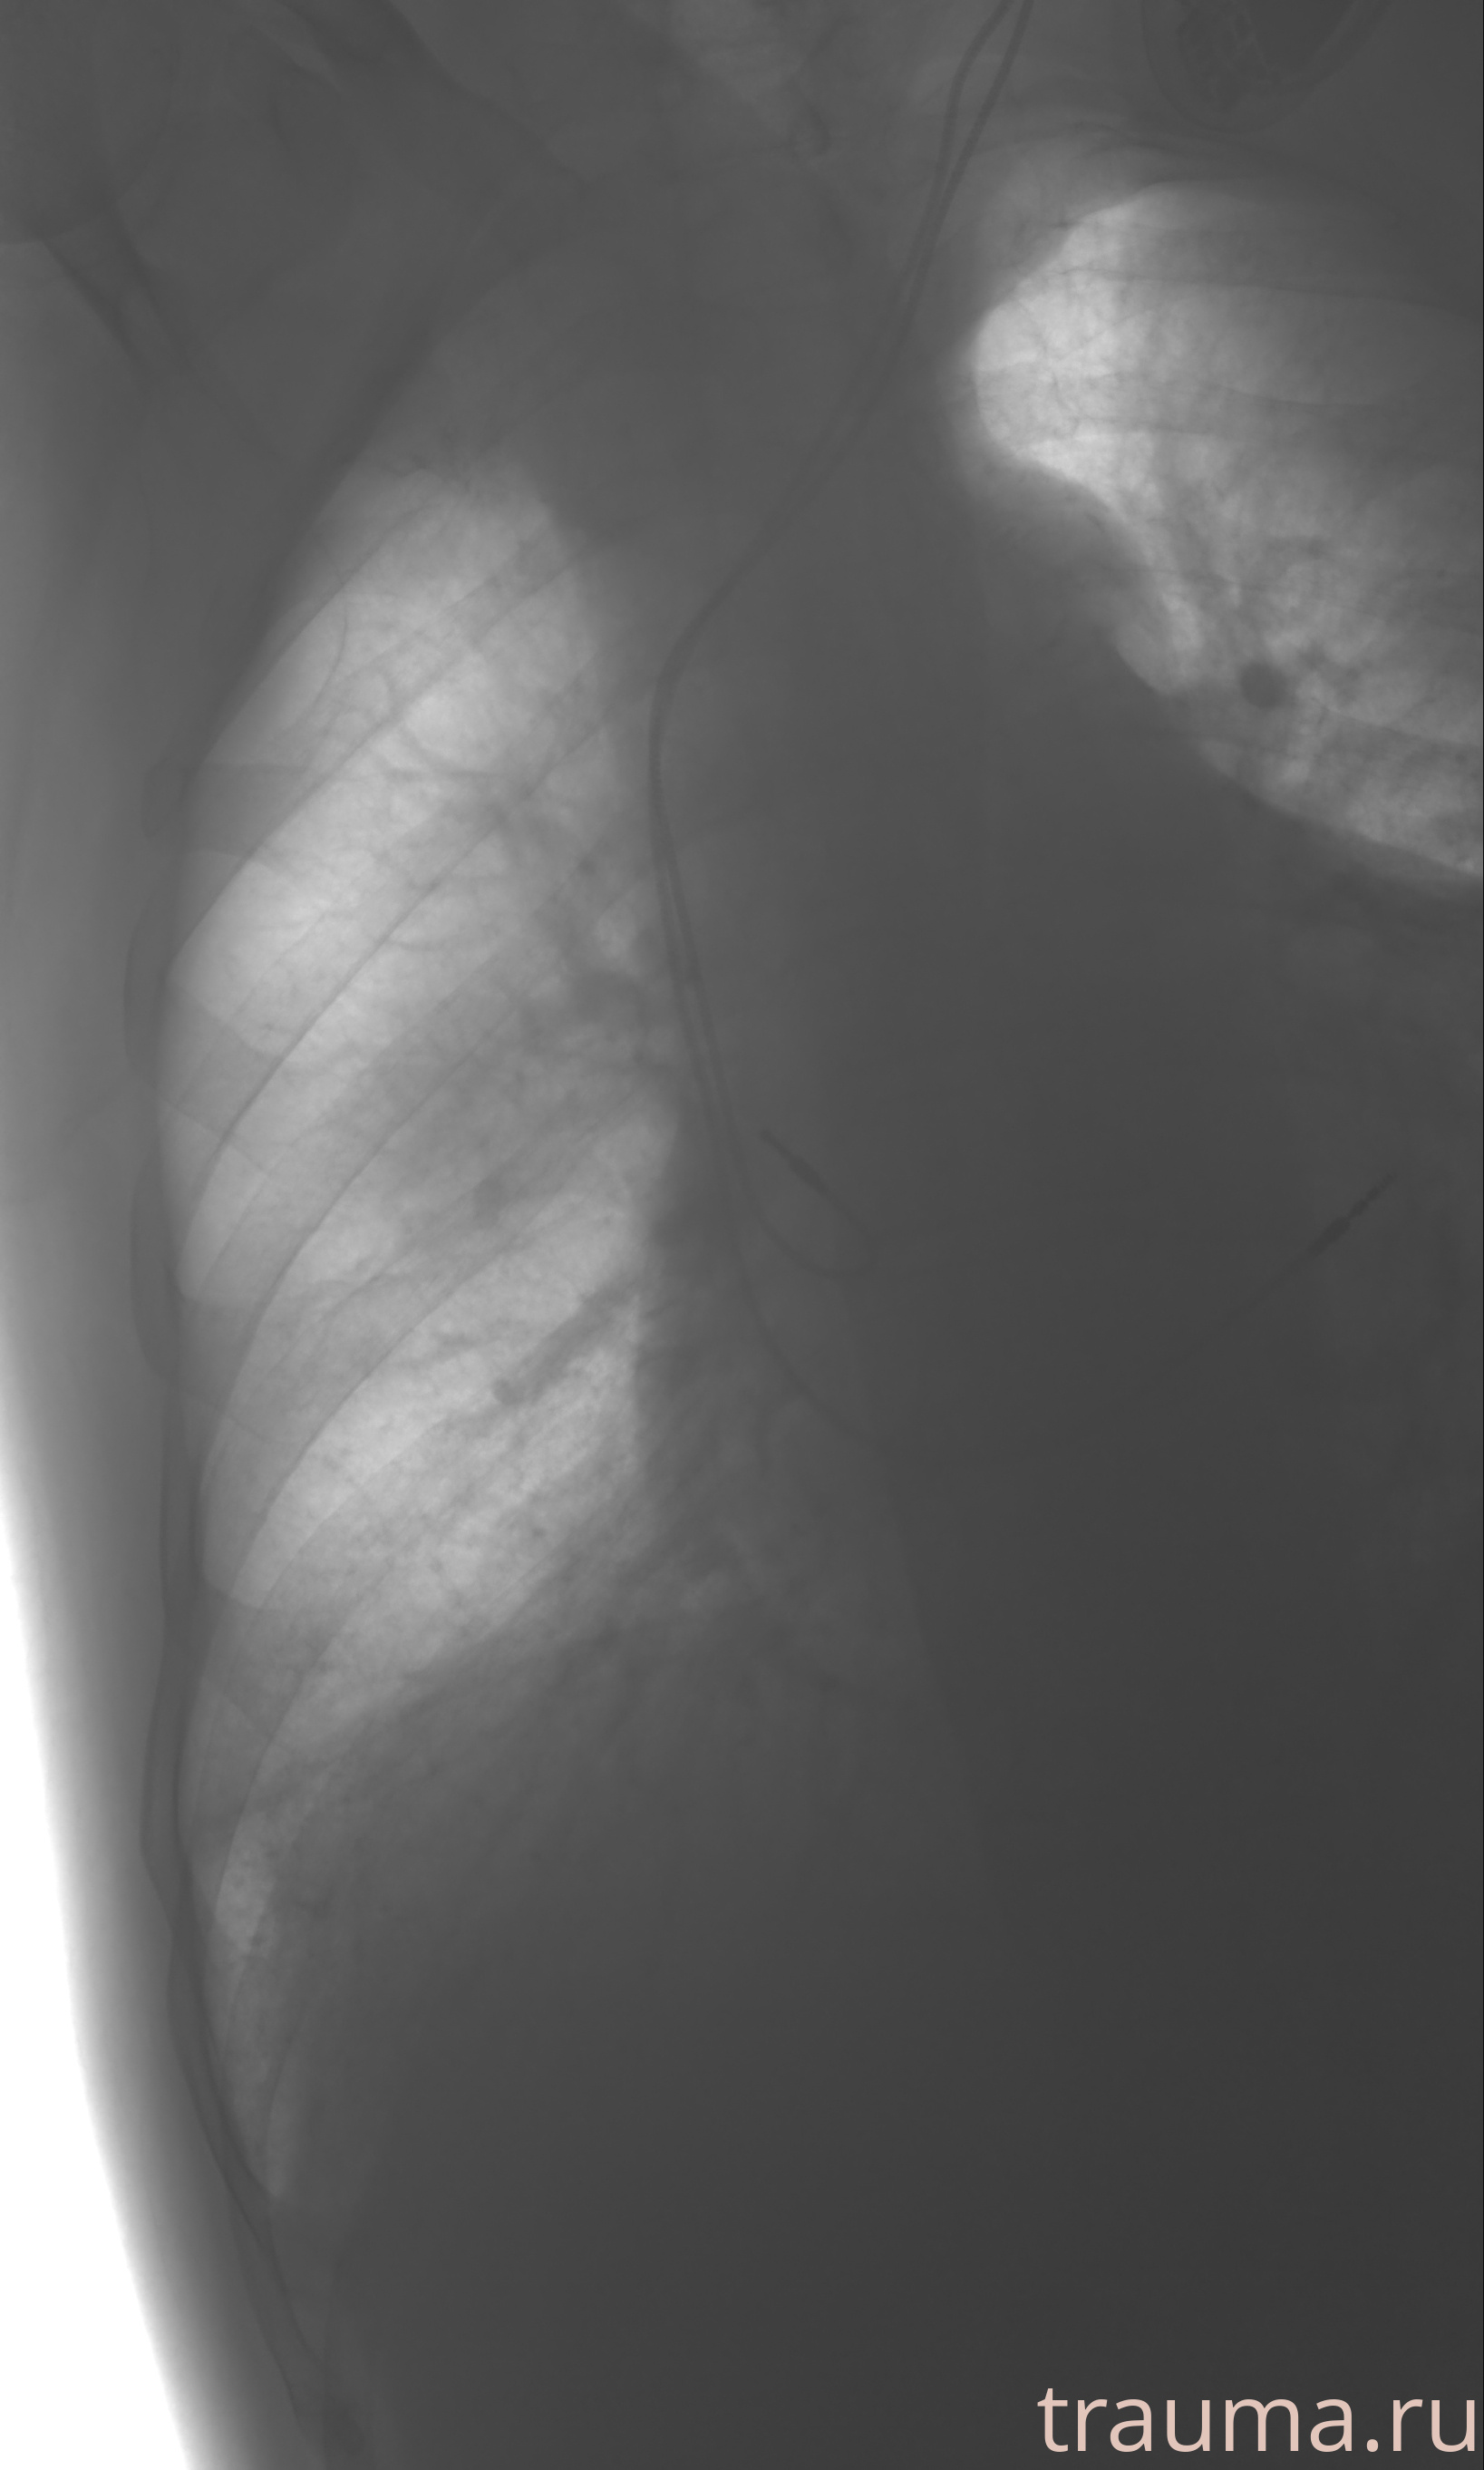

Рентген на дому: по вашему адресу приезжает врач-рентгенолог, травматолог-ортопед с мобильным рентгеновским аппаратом, проводит диагностику травмы или заболевания, делает необходимые рентгенограммы, дает рекомендации по дальнейшему лечению. Получить качественные снимки в домашних условиях возможно благодаря уникальной методике, разработанной МосРентген Центром для института  Склифосовского